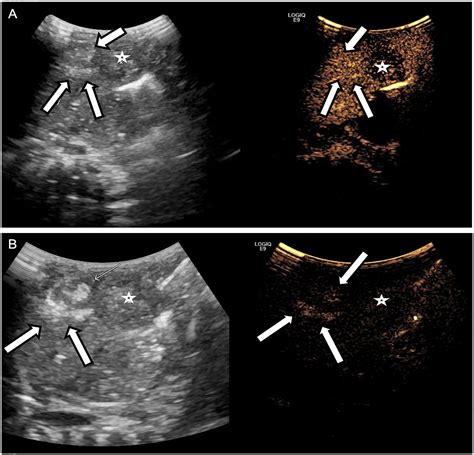

In the world of medical imaging, the liver is typically used as the "benchmark" for brightness. Healthy liver tissue has a specific texture and gray-scale appearance known as isoechogenicity. When an ultrasound technician scans the liver, they compare its brightness to the nearby kidney cortex and the spleen. If the liver appears brighter, darker, or more grainy than normal, it signals a change in the internal composition of the organ. The echogenicity of the liver is a direct reflection of how much sound energy is bouncing back to the transducer, which changes based on the presence of fat, fibrous tissue, or cellular swelling.

Radiologists categorize the liver's appearance into three primary grades based on how the echoes are reflected. Recognizing these variations is the first step in identifying underlying liver disease:

• Hyperechoic Liver: This occurs when the liver appears brighter than the kidney. It is the most common indicator of hepatic steatosis, or fatty liver disease, where fat cells infiltrate the liver tissue.

• Hypoechoic Liver: This happens when the liver appears darker than normal. This can occur in cases of acute hepatitis, where inflammation causes cellular swelling, or occasionally in specific types of infiltrative diseases.

• Isoechoic Liver: This represents the standard, healthy appearance where the liver’s brightness matches the surrounding anatomical structures.

• Non-Alcoholic Fatty Liver Disease (NAFLD): The accumulation of excess fat causes the liver to reflect more ultrasound waves, leading to increased echogenicity.

• Liver Cirrhosis: As the liver develops scar tissue (fibrosis), the architecture becomes coarse and irregular, often appearing brighter than a healthy liver.

• Hepatitis: Viral or autoimmune inflammation can change the cellular texture, sometimes resulting in a darker, "starry sky" appearance.